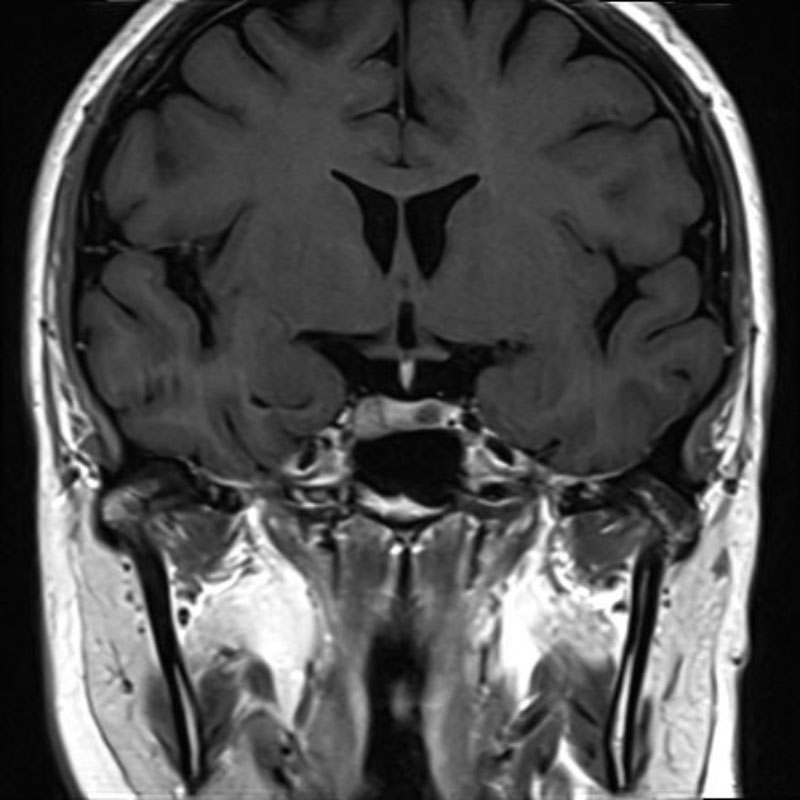

手術前1

手術前2